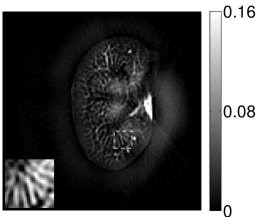

VI-E Results: kidney phantom

The images and EIRs reconstructed by use of the VP algorithm that was based on the 2D imaging model that neglected the SIR are shown in Figures 15 and 16. The latter figure contains results corresponding to different values for the regularization parameter . From Fig. 15, it can be observed that use of the conventional iterative method that utilized the measured EIR resulted in distortions and loss of details in the reconstructed images. Use of the VP algorithm improved the contrast and the details in the reconstructed images (Fig. 15(c) and 16(a)). Furthermore, the images reconstructed by use of the VP algorithm had a more uniform background.

In Figure 17, the results corresponding to use of the 3D imaging model that incorporated SIR effects are shown. The EIR estimated by the VP algorithm is also shown. In Figure 18, images and EIRs reconstructed by use of the VP algorithm with different regularization parameters values are shown.

Similar to the case described above where the transducer SIR was neglected, these results reveal that use of the VP algorithm can produce images with a cleaner background and enhanced spatial resolution than yielded by use of a conventional iterative algorithm that employed the measured EIR. For example, detailed information regarding the vessels near the organ’s periphery was better preserved by the VP algorithm than by the conventional iterative algorithm. These images corroborate our assertion that the VP algorithm can significantly reduce the artifacts and distortions in the reconstructed image. It is also worth pointing out that, unlike the numerical phantom studies, the artifacts and distortions in the images may be caused not only by the inaccurate EIR but also by other factors, such as neglecting acoustic heterogeneities and the variation of the EIRs among the elements of the transducer array. In such cases, the EIR estimated by the VP algorithm represents an effective system impulse response that minimizes the inconsistency between the measured data and the imaging model.